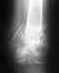

30.09.08 - закрытый вывих правого предплечья, закрытый перелом головки лучевой кости правого предплечья со смещением отломков.16.10.08 - Операция. Остеосинтез перелома головки лучевой кости винтом Герберта.Рука до сих пор полностью не разгибается. И ладонь не поворачивается вверх.. Есть ли надежда на то что она разработается полностью и будет полноценно функционировать? Нагрузку делаю полную, боли не тревожат. Единственное что напоминает о переломе так это не полное разгибание и движение кисти.Очень надеюсь на ваши ответы. Спасибо

Не видя снимка и не зная, как проводилась разработка, трудно отвечать определенно. Срок после травмы уже довольно большой, за это время обычно удается разработать все, что доступно.